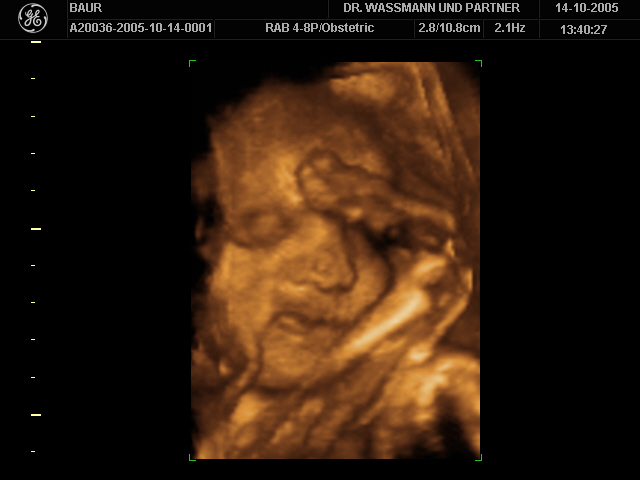

So, und jetzt noch ein 3D-Ultraschallbild unserer Kleinen von der 30. SSW. War gar nicht so einfach zu entscheiden welches ich euch zeige - sind doch alle so niedlich.

Susanne: Das "Bauchbild von innen" ist wirklich lieb. Ein süßes Mäuschen.